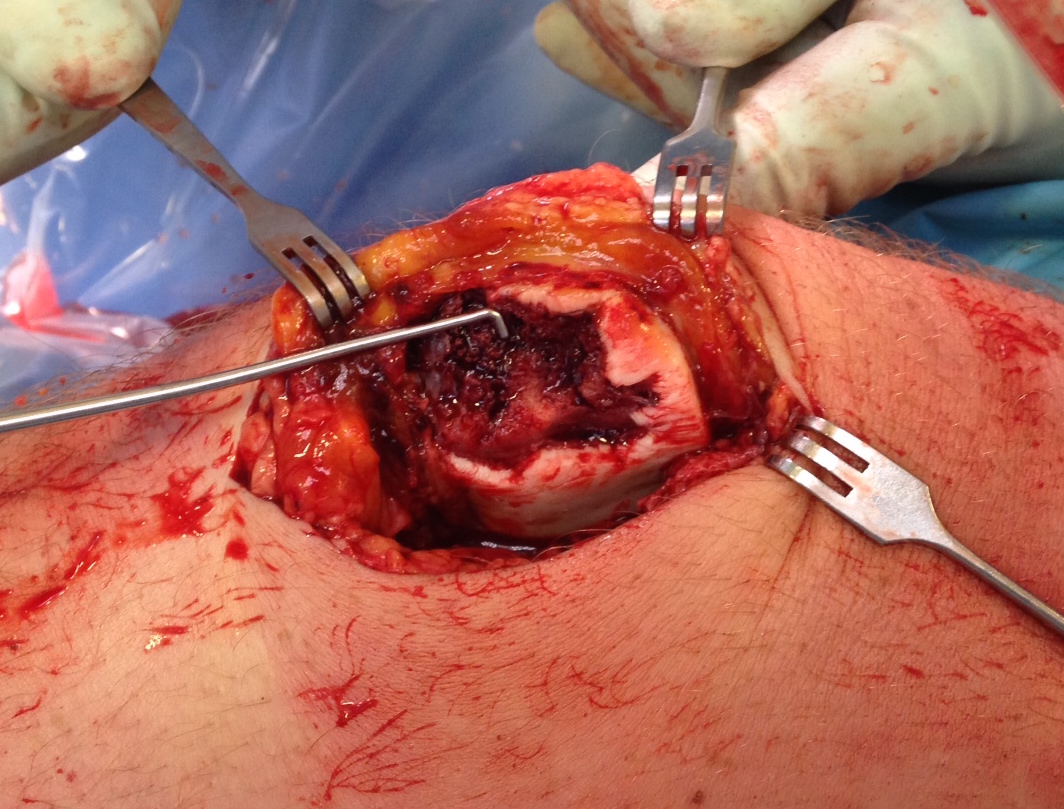

2. Large Osteochondral Fragment

- usually medial patella or lateral femur

- open approach to knee

- reduce and fix with bioabsorbable compression screws / pins